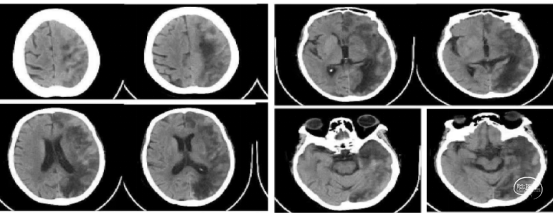

患者出现意识不清,病情加重。查CT左侧大脑中动脉区域水肿,低密度改变,中线移位。为大脑中动脉闭塞后改变,恶性脑水肿。

重症脑血管病管理:经甘露醇、白蛋白、3%氯化钠脱水、高压氧、依达拉奉、吡拉西坦脑保护治疗13天水肿消退,脑中线无移位,左侧大脑中动脉区域较前变淡。脑沟脑回显示清楚。

患者意识清楚,部分感觉性失语(部分听不懂),能说话,左侧肢体功能正常,配合指令活动。右侧上肢肌力0级,下肢肌力Ⅱ级+。